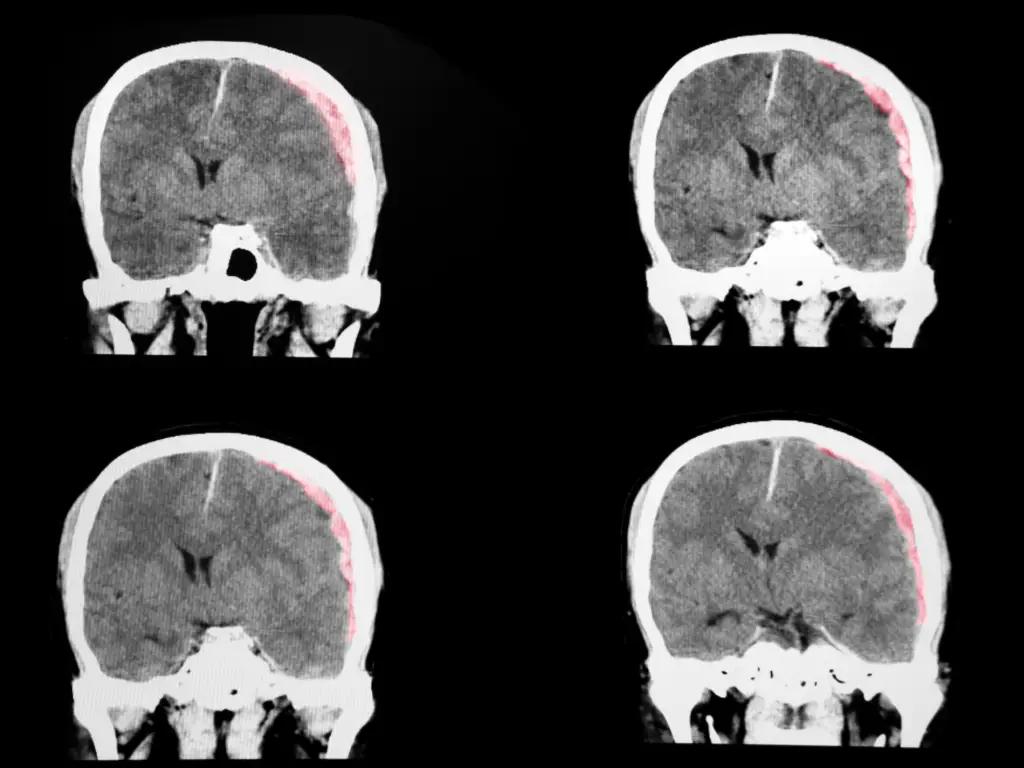

The US National Academies of Sciences, Engineering, and Medicine (NASEM) released a report in 2022 outlining recommendations to improve research and care for people with TBI. In it, they included a call for the development and dissemination of a classification system for TBI that incorporates not only the GCS score but also brain imaging and other prognostic biomarkers and for patients to be reclassified regularly during the treatment and recovery periods.

Under the guidance of a Steering committee, six working groups have been developed and populated with some of the world’s best experts. The goal of the classification and nomenclature effort is to inform the development of more precise evaluation guidelines, to create an evidence-based classification system that goes beyond the terms “mild, moderate, severe,” and to identify ways to reclassify patients during and after their recoveries. Stay tuned for more developments. In the meantime, read the NASEM study!